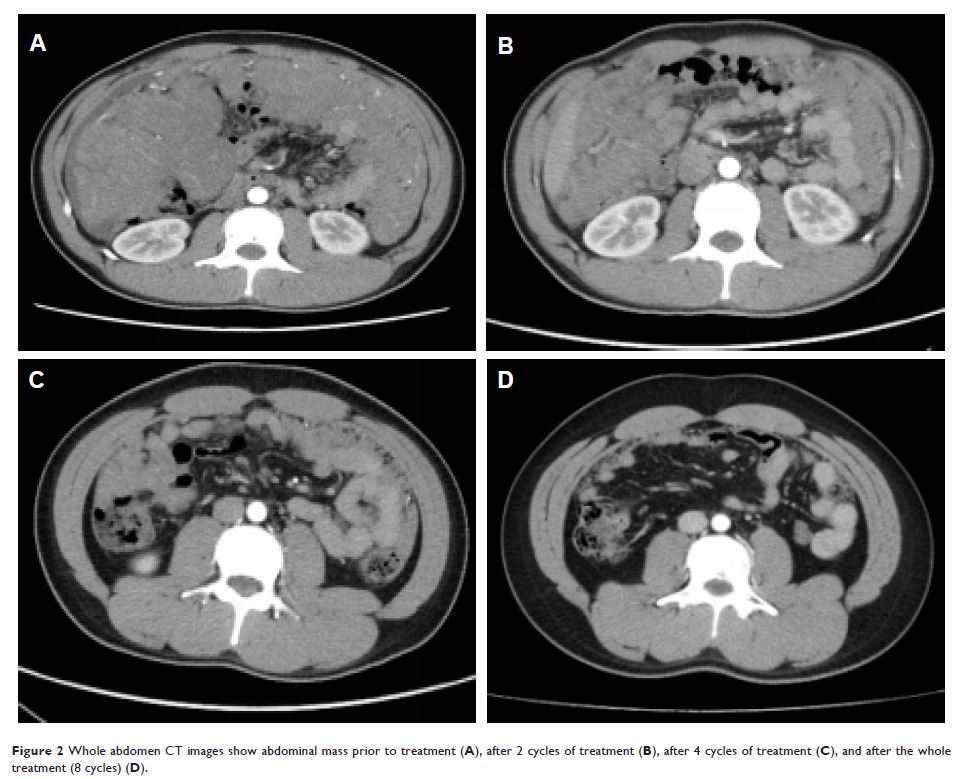

重组人血管内皮抑制素(恩度)和传统化疗成功治疗复发性睾丸胚胎性横纹肌肉瘤:一份病例报告